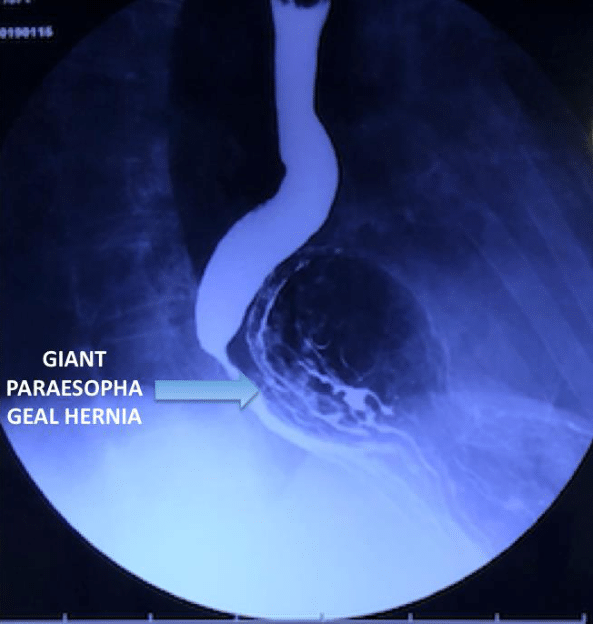

A 73-year-old male patient with a history of laparoscopic bilateral inguinal hernia repair twenty years before, and laparoscopic antireflux surgery 18 years before. Eleven years later he presented episodes of belching, heartburn, and continuous fermented food smell which were progressive. Endoscopy at that time revealed a large paraesophageal hiatal hernia which was treated with proton pump inhibitors, prokinetic medication, and dietary restrictions. His symptoms progressed until he was almost unable to eat, and came to the clinic due to intense continuous postprandial substernal pain and dysphagia. An endoscopy and an upper gastrointestinal (GI) series were performed, which showed a giant HH with a complete thoracic gastric volvulus. He underwent a laparoscopic procedure, performing hiatal repair with mesh placement and a Nissen fundoplication, which corrected the symptoms. Five months later, he presented again an acute intense substernal pain, significant upper abdominal distention, profuse salivation, and severe dysphagia. The upper GI series revealed a giant recurrent HH and a mesenteroaxial gastric (Figure 1) volvulus with complete obstruction to distal pass of contrast media. Due to his medical history, evident weakness of the hiatal tissues, and the possibility of a new recurrence, it was discussed with the patient to perform a PSG of the gastric body and fundus to lengthen the esophagus, which was accepted by the patient and his family. By laparoscopy, the herniated gastric volvulus (Figure 2) was reduced and a PSG was performed leaving the hiatus open (Figure 3). The mesh was left in situ as it was completely epithelized. His postoperative recovery was adequate, the postoperative upper GI series showed adequate transit of the contrast medium (Figure 4). Two years after this surgery he is well, does not report any symptoms related to reflux or dysphagia, doesn’t take any medications, his diet is normal and he carries out his daily activities normally.

Figure 1 ThreeUpper GI series reveled a giant hiatal hernia with mesenteroaxial gastric volvulus recurrence.

Figure 2 Giant hiatal hernia with gastric volvulus.